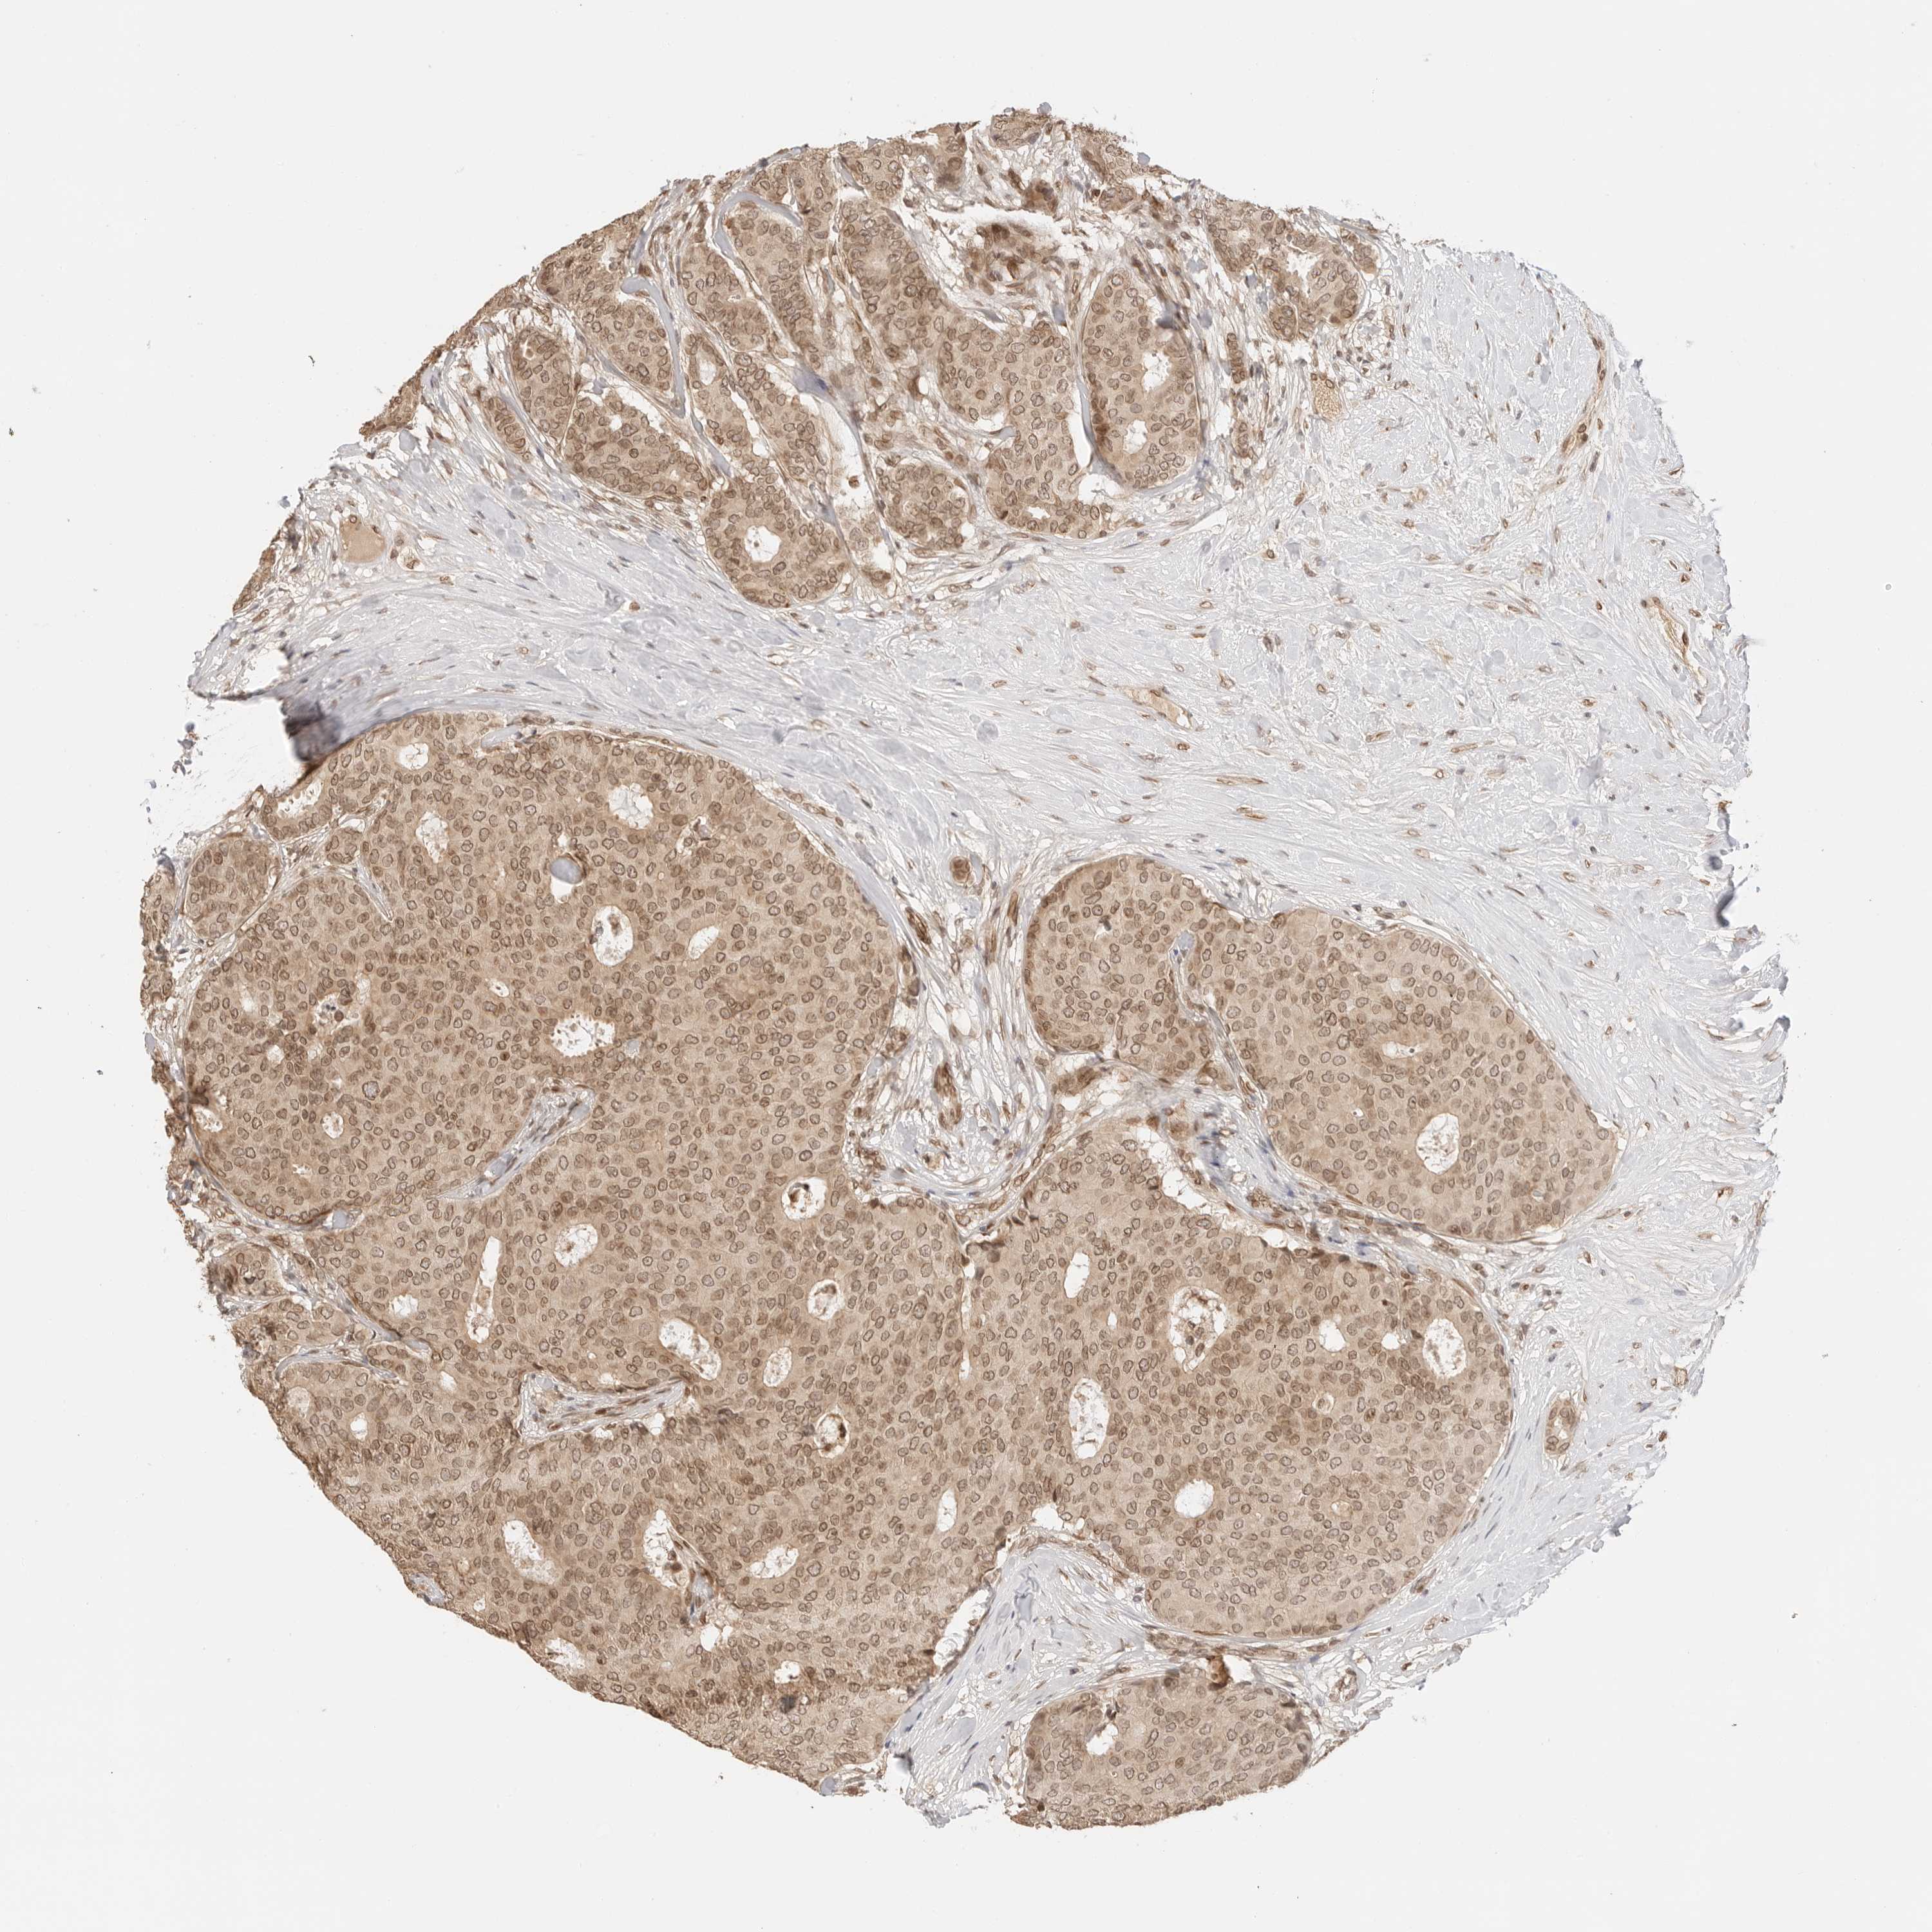

BRCA TCGA BRCA VALIDATION PROTEIN EXPRESSION

ANTIBODIES

AND

VALIDATION